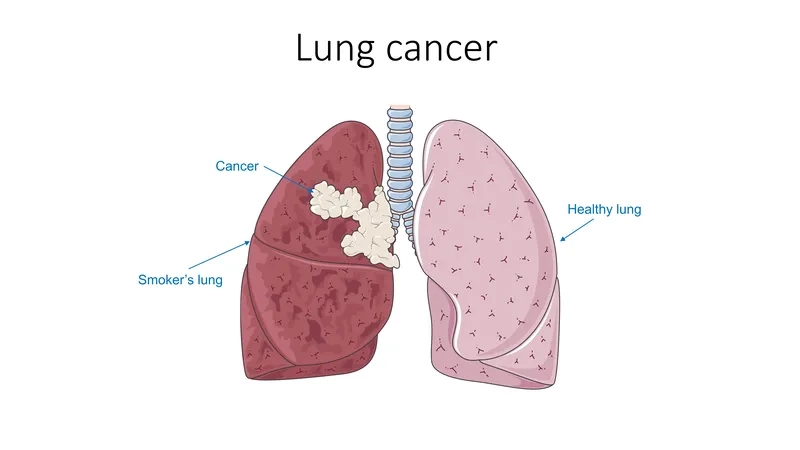

- The primary cause of lung cancer is smoking tobacco, which is responsible for the vast majority of cases in both non-small cell and small cell types.

Image of the disease Lung Cancer - and other variables